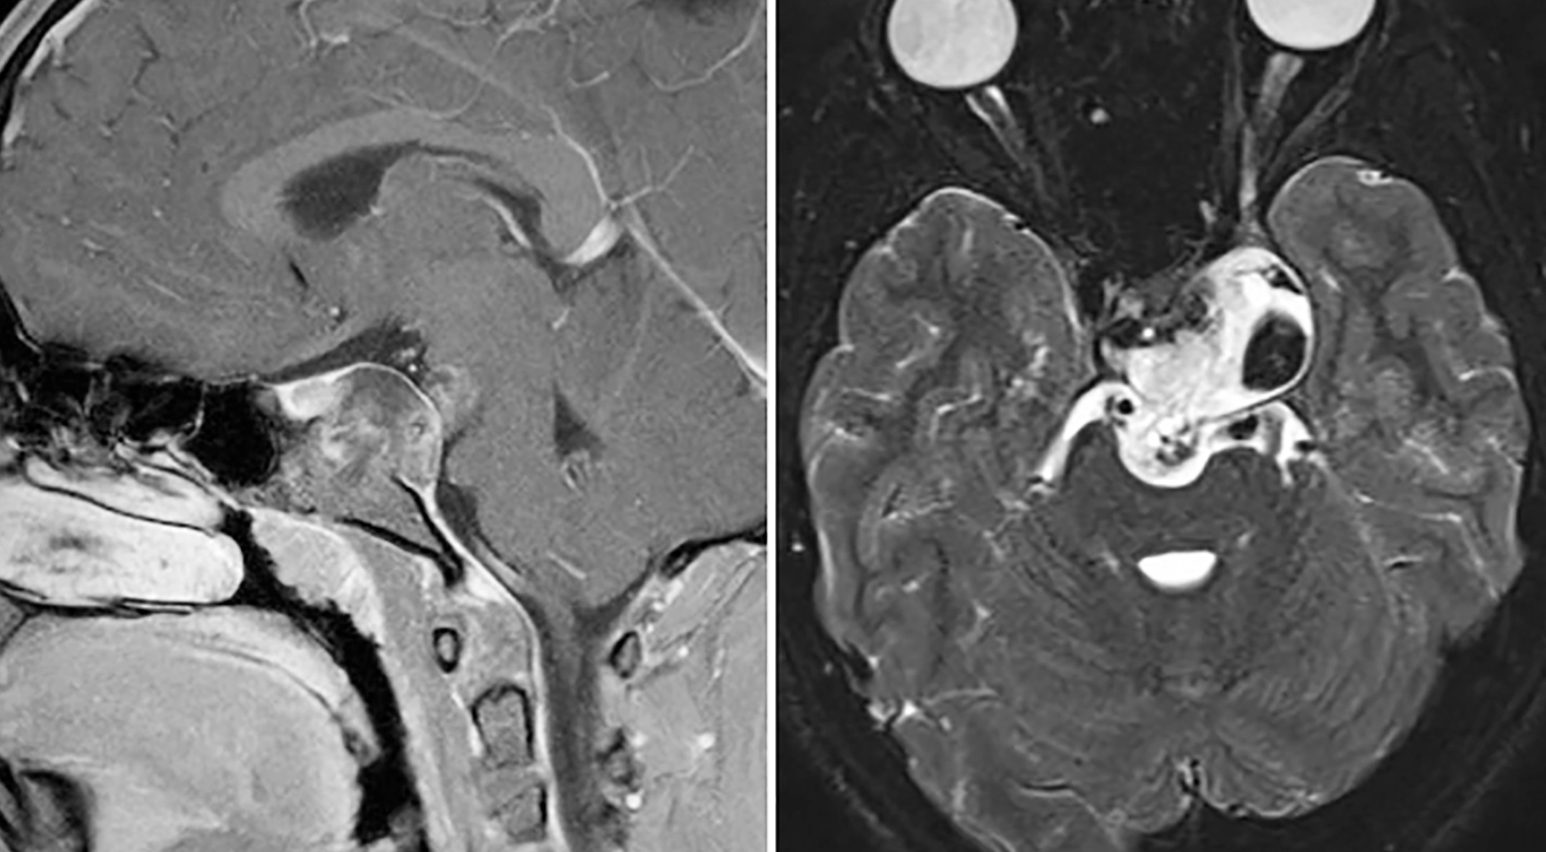

malformación de Chiari

siringomielia